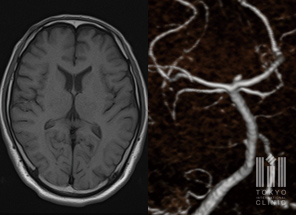

頭部MRI/MRA検査

CTよりも鮮明な画像を得られるため、脳血管障害の早期診断に有効です

- 頭頚部MRI/MRA